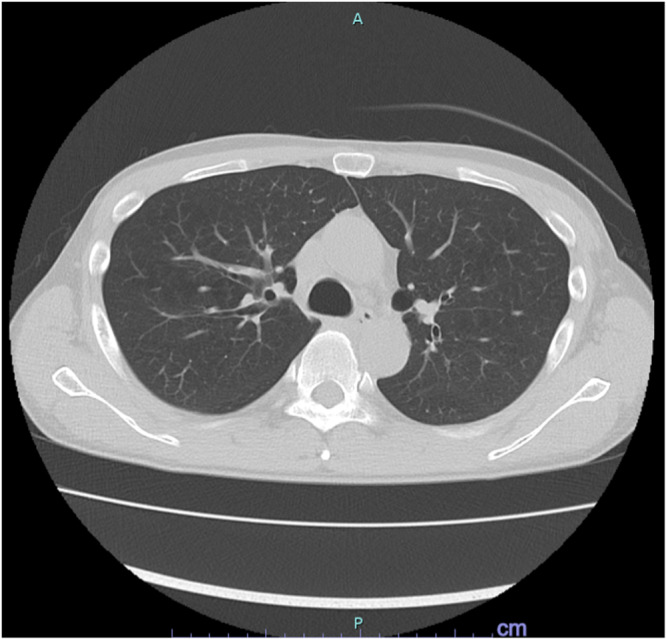

Case presentation: We present a case of a 51-year-old man with schizophrenia who developed CLIA complicated by IPA. The patient, diagnosed with treatment-resistant schizophrenia, was started on clozapine, but 9 months later he presented with fever, cough, leukopenia, and neutropenia. Clozapine was discontinued, and empirical treatments with cefepime and filgrastim were initiated. Serum β-D-glucan and Aspergillus galactomannan antigen tests were positive, and chest CT showed well-circumscribed nodules, leading to a probable diagnosis of IPA. Antifungal therapy was switched from micafungin to voriconazole according to guidelines. His neutropenia and fever improved, and he was re-transferred to a psychiatric hospital.